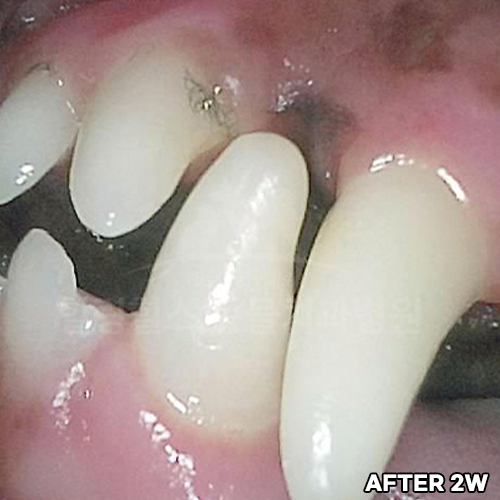

[강아지발치] 잇몸뼈가 녹은 구멍에 자기잇몸뼈가 튼튼하게 재생되어 채워졌어 - 강아지치아발치 2년 후 구강X-ray 비교! -

2025.11.26